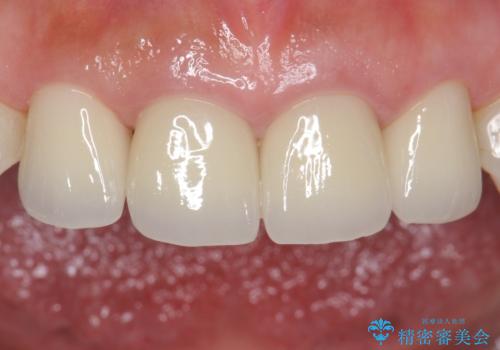

- 右上12左上12/仮歯4本+ジルコニアクラウン4本:44,000+484,000円 左上2/根管治療(保険)費用は治療当時の料金となります

歯ぐきの炎症を抑えつつ、被せ物と歯との境目がわからなくなるよう被せ物を装着しました。

審美性が大変改善されたことで患者様にもご満足いただけました。